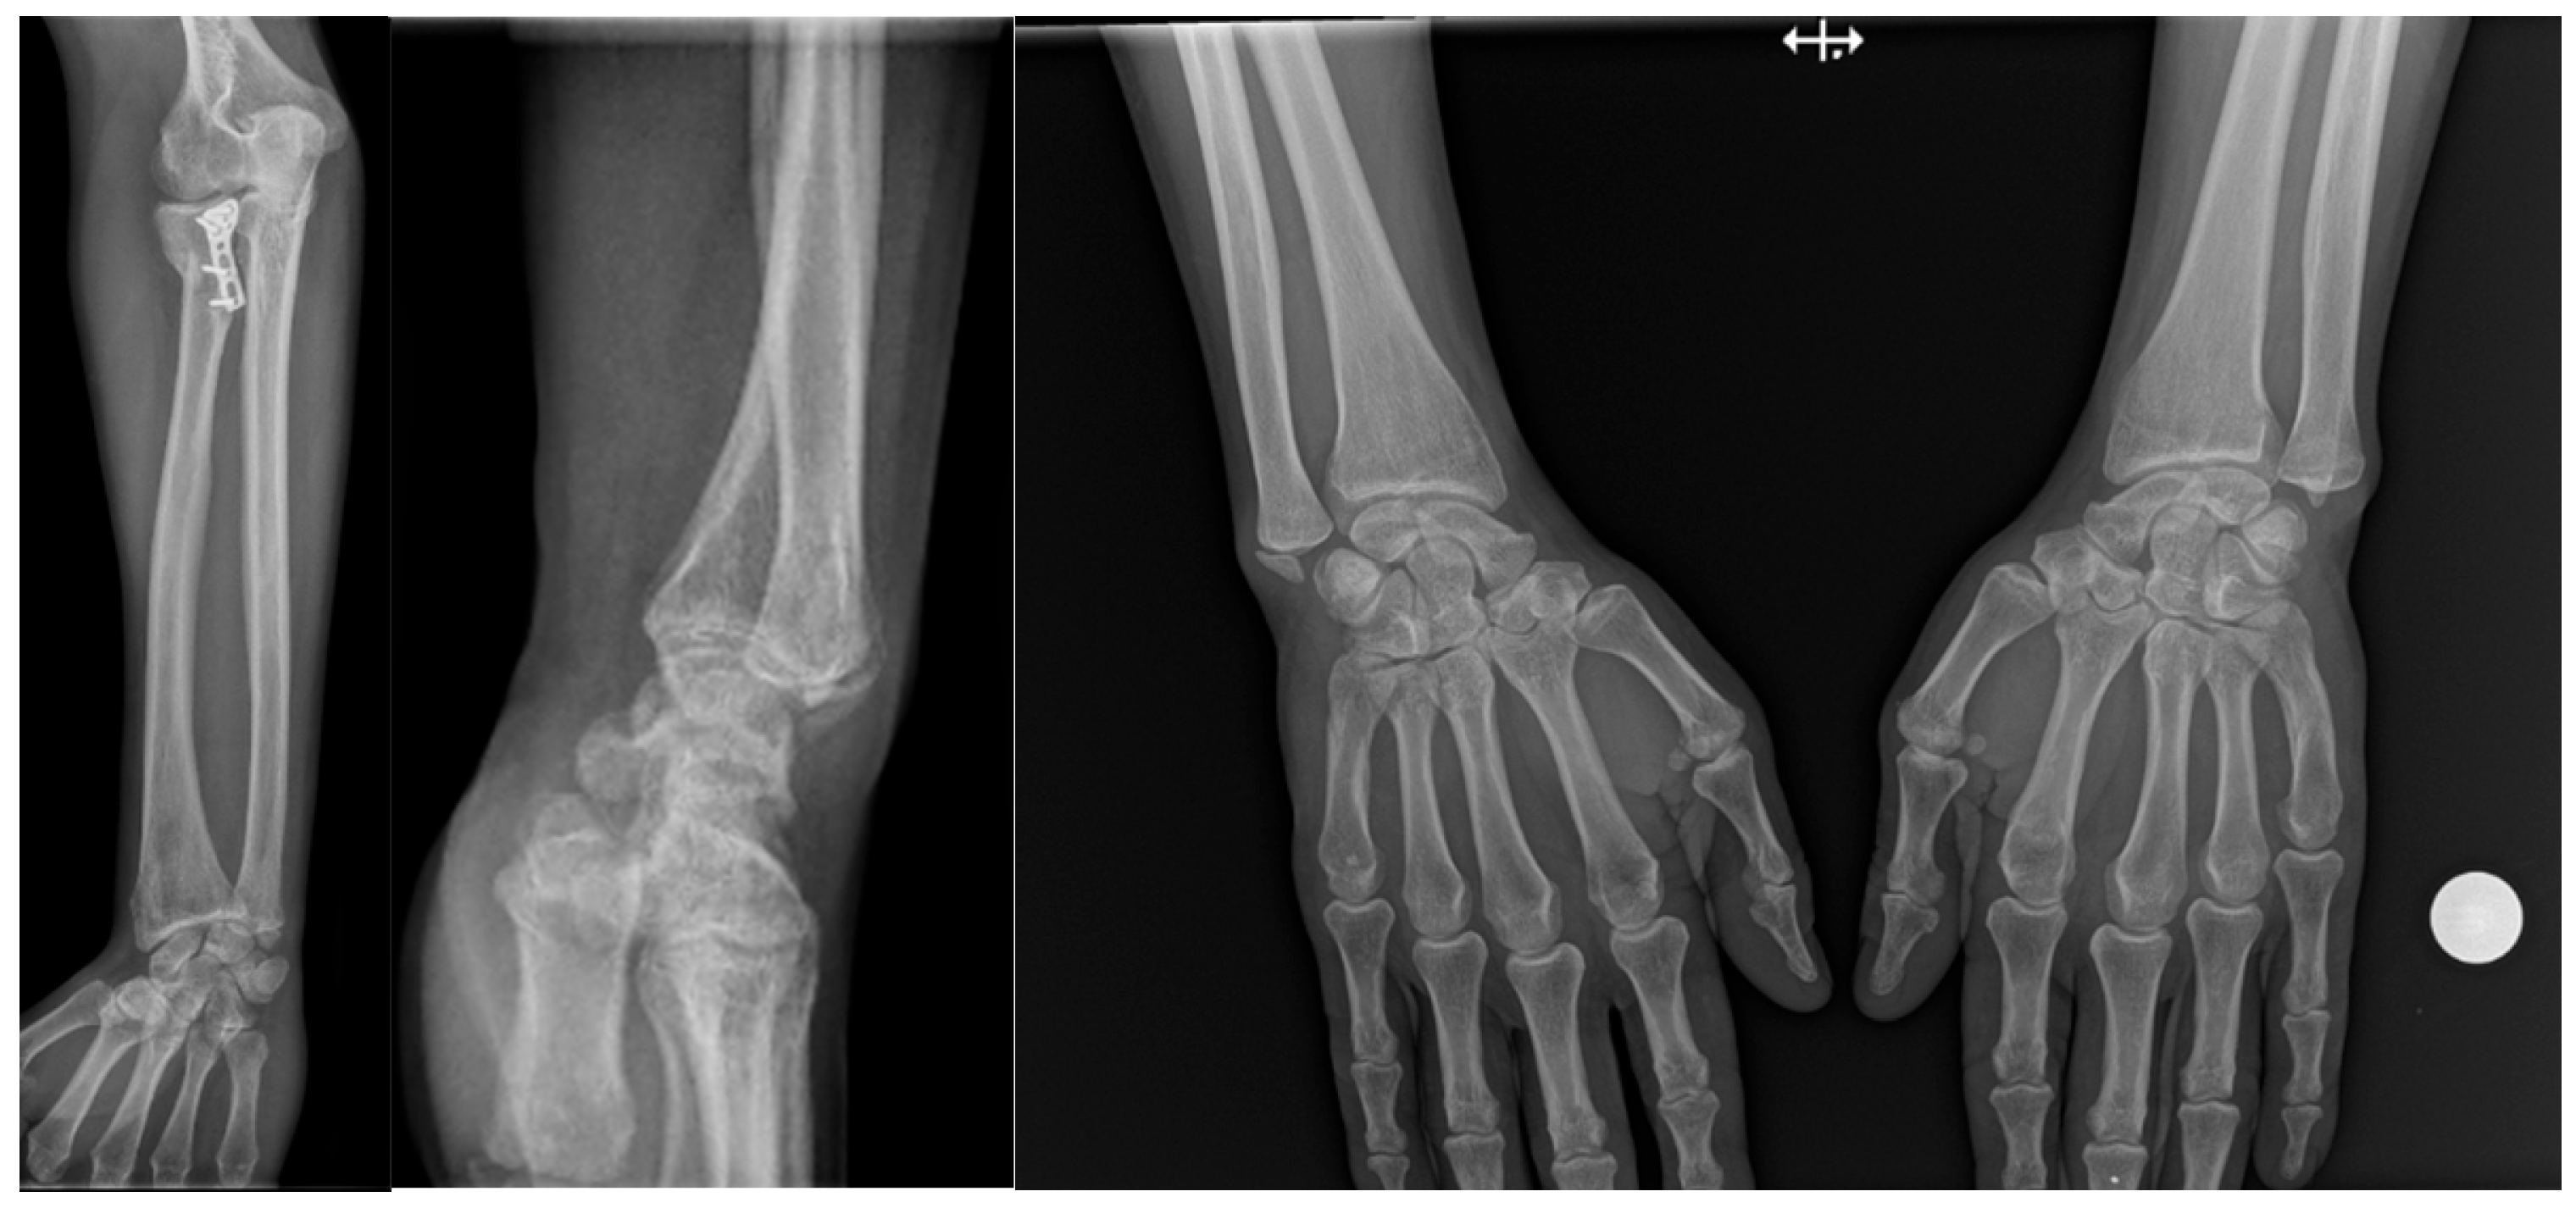

The study included forty-five patients diagnosed with injuries of the distal radioulnar joint and treated at Saint Spiridon Hospital in Iași, Romania. The cases were selected to represent the full spectrum of traumatic patterns associated with DRUJ instability [9,10]. Twenty patients had distal radius fractures, twenty presented Galeazzi fractures, and five were diagnosed with Essex Lopresti injuries (Figure 1).

Figure 1.

Essex Lopresti lesion treated with radial head plate fixation, associated with ulnar styloid fracture and dorsal displacement of the ulnar head. The increased DRUJ gap and positive ulnar variance compared with the contralateral side indicate a grade 2 DRUJ injury.